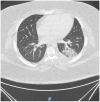

A Unique Presentation of COVID-19 in a Patient Post Sleeve Gastrectomy